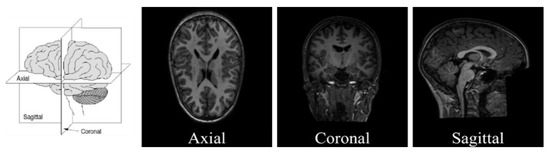

- Extracting 1, 10, and 50 slices along each brain plane (axial, sagittal, and coronal) to generate sequences of 2D images from raw 3D sMRI scans.

- Extracting 10, 30, and 50 slices along all brain planes (axial, sagittal, and coronal) to generate sequences of 3D images from raw 4D fMRI scans.

- Extracting all slices or giving some exceptions to the beginnings and the ends along all brain planes (axial, sagittal, and coronal) to generate sequences of 3D images from 3D sMRI and 4D fMRI scans.